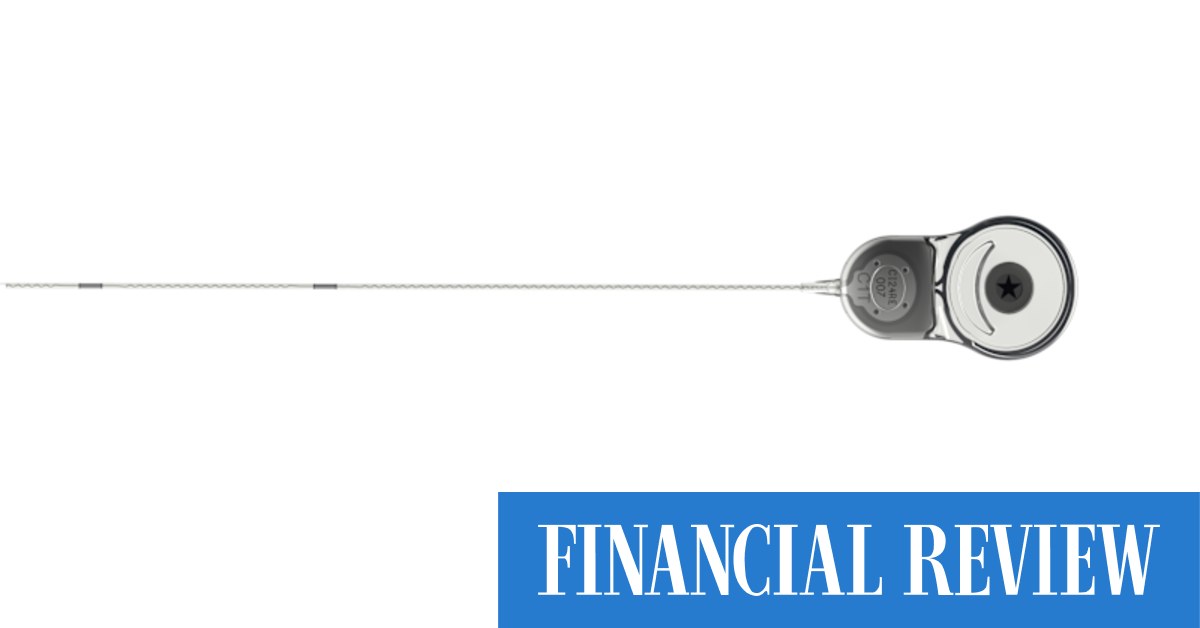

ASX-listed hearing implant giant Cochlear has deepened its exposure to Epiminder as the Melbourne maker of scalp monitoring technology opens its initial public offering book to investors.

The Minder can slip beneath the scalp and monitor the brain.